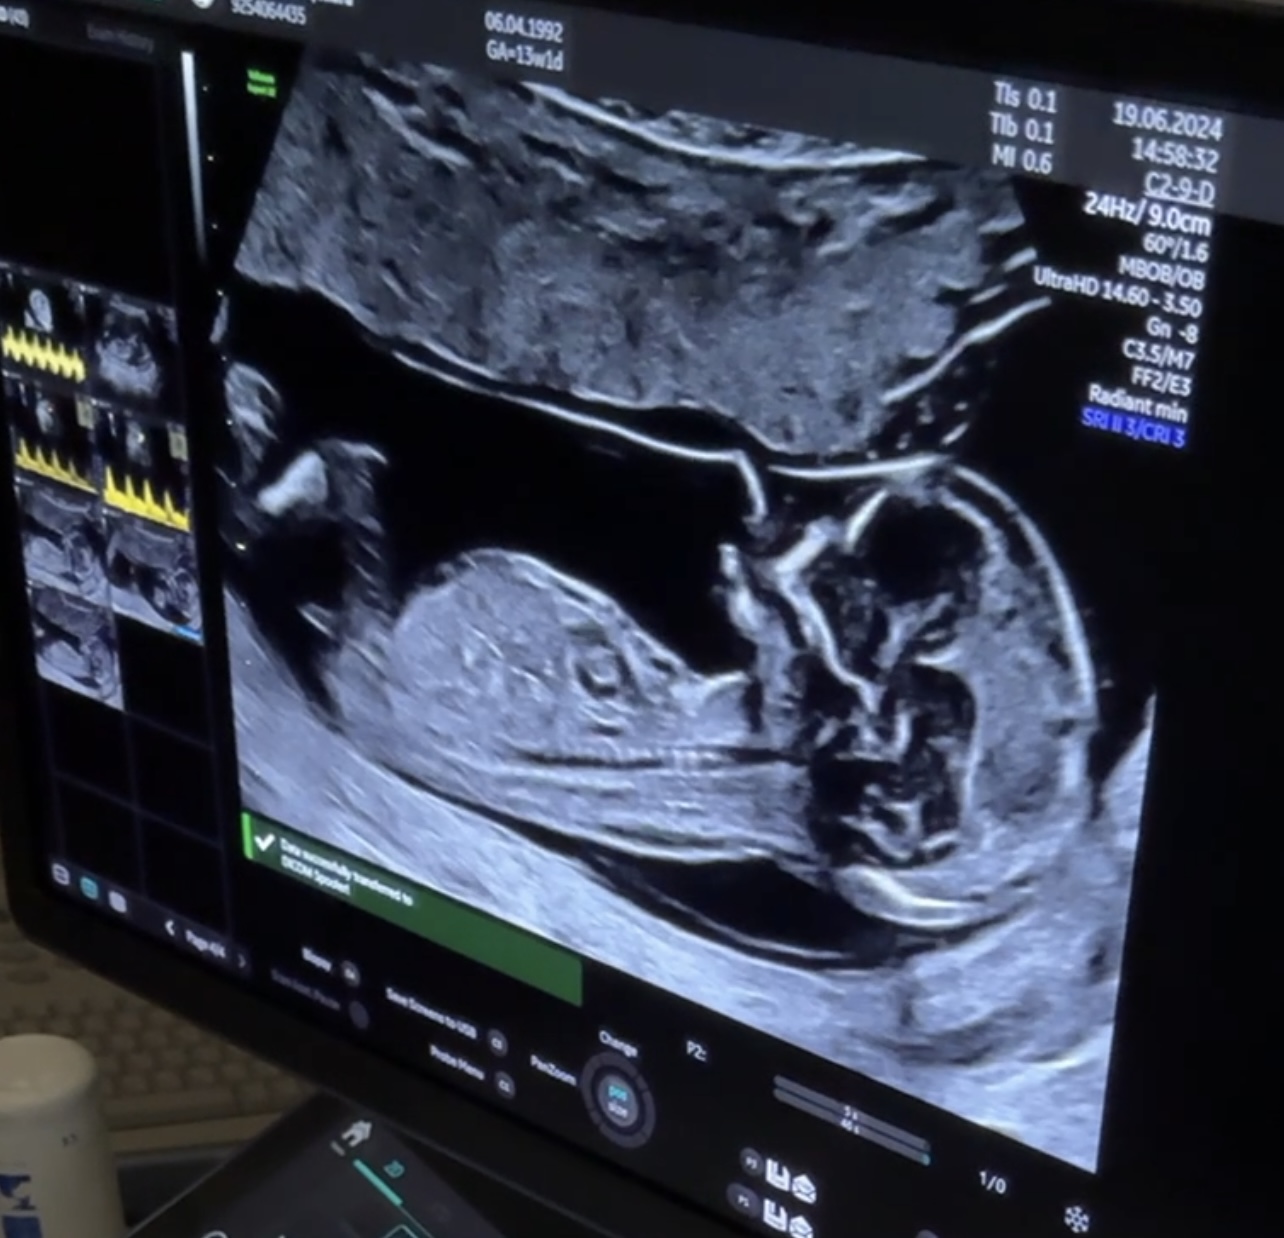

Asi záleží i na tom, na jakém pracovišti a s jakým přístrojem se ultrazvuk provádí. Na prvním screeningu nám doktor z brněnského Prenatalu už před 8 lety ukázal na monitoru - Co vidíte? Bylo tam jasné kávové zrno. Tak prý ano, jasná holčička. U druhého dvojčátka to samé. A mám dvě holky, nebylo žádné na kolik procent, fakt to bylo vidět i laickým okem.

@lilian2111 Mně přijde taky spíš jako holka, i když ne zcela jednoznačně.

Holka 😀 mam doma, na lednici, stejnou fotku a v postylce spi skoro 5mesicni dcerka ❤️